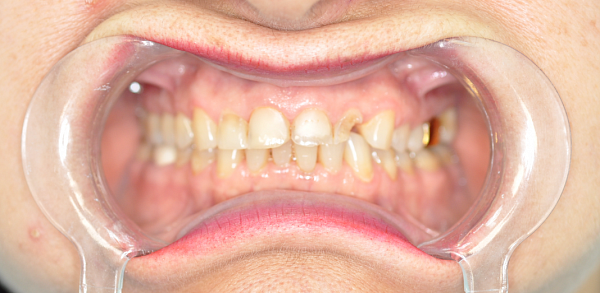

Пациент, 54 года. Замена старых металлических протезов на диоксид циркония.